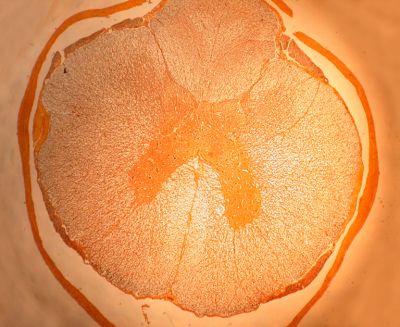

Spinal cord - histology slide

This histology slide is from the spinal cord.

Histology slide courtesy of Florida State University.

Central Nervous System Histology - Spinal Cord